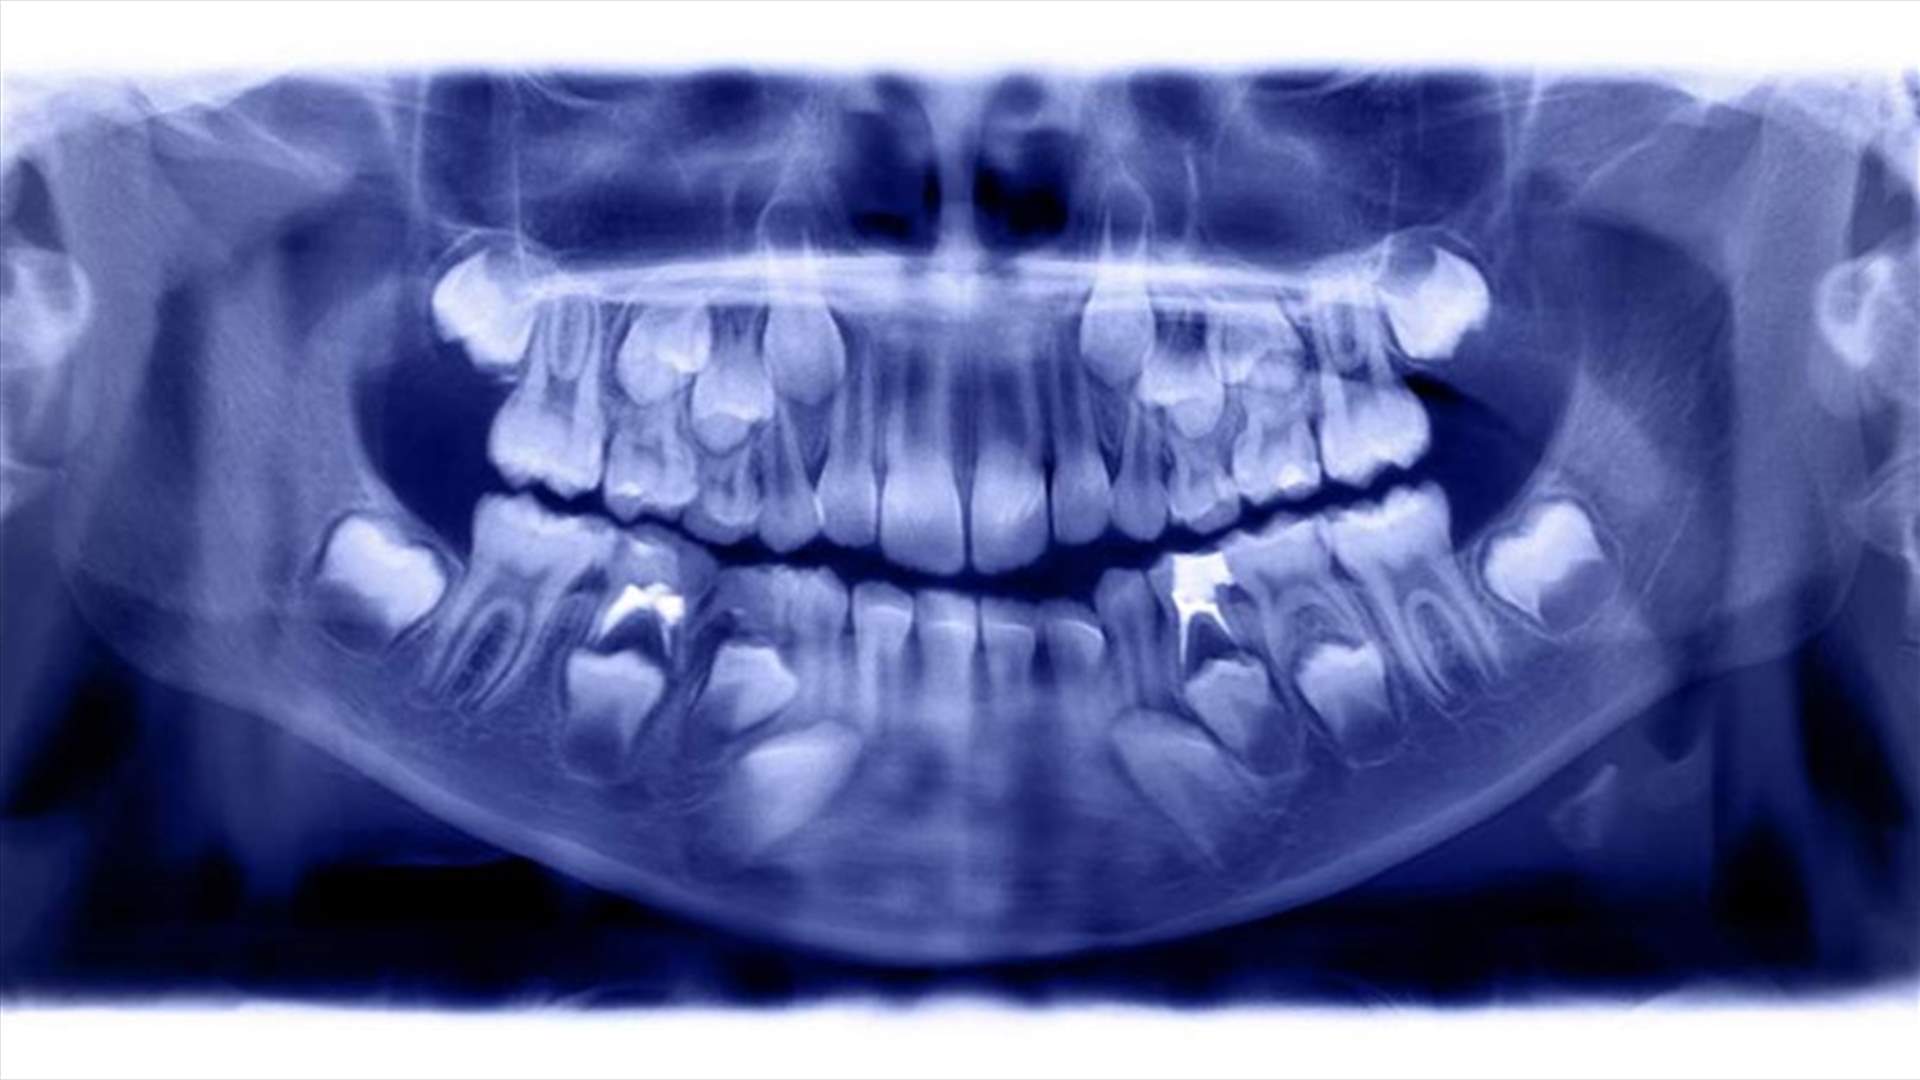

حالة طبية تثير الذهول... الأطباء يقتلعون أكثر من 500 سن من فم طفل

أفاد أطباء أسنان من الهند يوم الأربعاء الفائت، أنهم اقتلعوا أكثر من 500 سن وضرس وناب من فم طفل عمره سبع سنوات، يعاني من حالة طبية غير عادية.

فقد تم نقل الطفل ر. رافيندران إلى كلية ومستشفى سافيثا للأسنان في شيناي، حيث عولج من تورم في الفك الأيمن السفلي منذ أن كان عمره ثلاث سنوات.

وبعد تصويره بالأشعة، اكتشف الأطباء نمواً كبيراً شبيهاً بالكيس يحتوي على هياكل صلبة متعددة في الفك ووصفوا حالته بالورم المركب بالأسنان.

وقالت الدكتورة براتيبا راماني، أستاذة ورئيسة قسم أمراض الفم والوجه والفكين لصحيفة التايمز أوف إنديا: "لم نر هذا العدد من الأسنان في موقع واحد من قبل".

فقرر الأطباء إجراء جراحة ضرورية لعلاج هذه الحالة النادرة، واستغرقت العملية خمس ساعات لإزالة 526 سناً من "الكيس" في الفم.